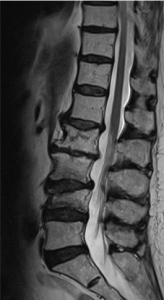

Degenerative Bandscheibenerkrankung

Hierbei handelt es sich um einen altersbedingte Veränderungen des Bandscheibenkerns, d. h. die Pufferfunktion der Bandscheibe nimmt ab. In der Folge kommt es zu Strukturveränderungen der Bandscheibe sowie zu Rissbildungen mit erhöhter Druckbelastung der Wirbelkörperendplatten mit anschließendem Verschleiß.

Das Ziel einer Wirbelsäulenoperation bei degenerativen Veränderungen ist die Schmerzlinderung durch Entlastung der Nerven bei Einengung, die Wiederherstellung des ursprünglichen Profils der Wirbelsäule und eine Ruhigstellung.

Spinalkanalstenose

Die Spinalkanalstenose ist eine zunehmende dynamische Einengung des Wirbelkanals auf Bandscheibenniveau durch überwiegend degenerative Veränderungen der Bandscheibe, der Wirbelkörperendplatten, der Zwischenwirbelgelenke sowie der umgebenden Bandstrukturen mit und ohne begleitende Instabilität des betroffenen Bewegungssegmentes. Die Lendenwirbelsäule ist hiervon häufiger als die Halswirbelsäule betroffen.

Osteoporotische Fraktur

Der Bruch eines oder mehrerer Wirbelkörper bei erniedrigter Knochendichte (Osteoporose) ist einer der häufigsten Brüche im Alter. Die Wirbelkörper können ohne adäquate Ursache im Rahmen von Alltagsbelastungen brechen und starke Schmerzen verursachen. Am häufigsten ist die untere Brustwirbelsäule bzw. der Übergang Brust-/Lendenwirbelsäule betroffen. Zusätzlich können Fehlstellungen der Wirbelsäule und Lähmungserscheinungen resultieren.